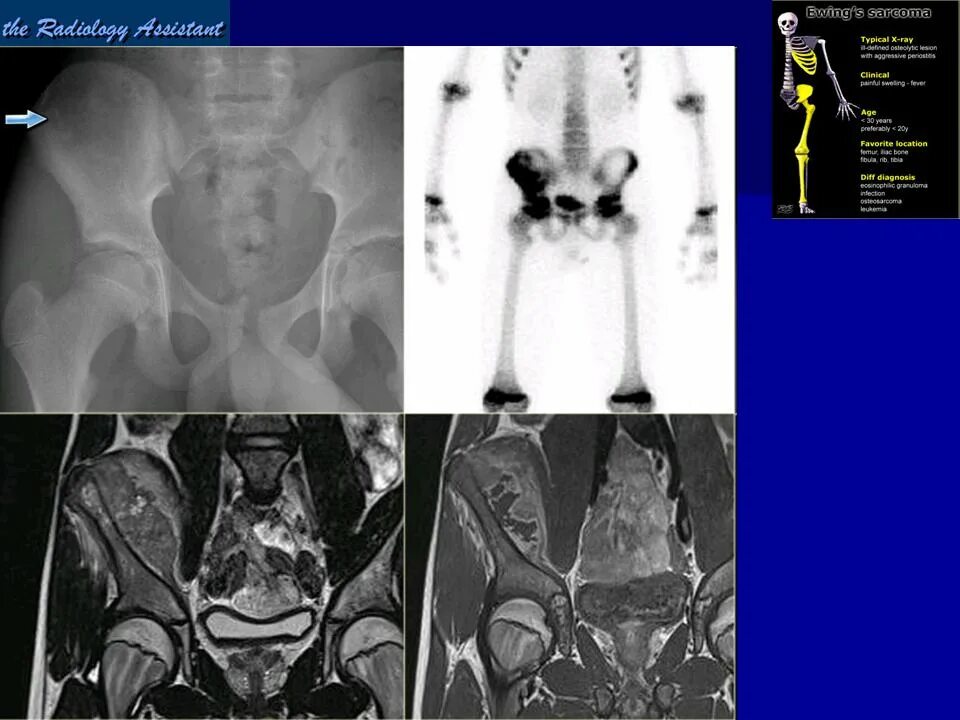

Саркома мрт